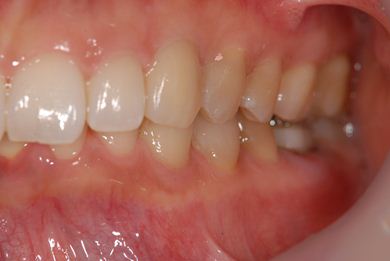

性別/年齢 女性 / 37歳

主訴 歯の差し歯が少しぐらつく。歯ぐきが違和感を感じる。

治療方針 抜歯と同時にインプラントを埋入し、治療期間を短縮する。

治療内容 インプラント1本(抜歯即日スピードインプラント)、メタルボンドセラミック1本

治療前

• 治療前